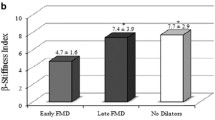

Subjects’ physiological characteristics and hemodynamic parameters are presented in Table 1. As shown in Fig. 1, with advancing age, carotid arterial %distension and distensibility coefficient were deceased (r = −0.696 and r = −0.722, p < 0.0001 for both), whereas β-stiffness index was increased (r = 0.661, p < 0.0001). Carotid arterial diastolic diameter and pulse pressure did not correlate with age (r = −0.037 and r = 0.120, respectively). Carotid arterial peak BFV, pulsatile BFV, and the normalized pulsatile BFV significantly correlated with age (r = −0.453 to −0.600, p < 0.0001 for all), whereas mean and minimum BFV were not influenced by age (Fig. 2).

Peak BFV, pulsatile BFV, and the normalized pulsatile BFV was significantly correlated with %distension (r = 0.367–0.624, p < 0.001–0.0001), whereas mean and minimal BFV did not correlate with %distension. No measurements of carotid arterial BFV were correlated with carotid pulse pressure. As shown in Table 2, distensibility coefficient of carotid artery correlated with peak BFV (r = 0.305, p < 0.01), pulsatile BFV (r = 0.406, p < 0.0001), and the normalized pulsatile BFV (r = 0.591, p < 0.0001). Multi-regression analysis revealed that age, heart rate, and lumen diameter, pulse pressure, and the normalized pulsatile BFV of carotid artery were significant independent determinants of distensibility coefficient. Likewise, β-stiffness index correlated with peak BFV (r = −0.281, p < 0.05), pulsatile BFV (r = −0.374, p < 0.01), and the normalized pulsatile BFV (r = −0.530, p < 0.0001). Multi-regression analysis revealed that age, heart rate, estimated VO2max, mean arterial pressure, and carotid arterial lumen diameter and the normalized pulsatile BFV were significant independent determinants of β-stiffness index.

Aggregate evidence suggests that the lowered distensibility of central elastic arteries could be a risk for cardiovascular and cerebrovascular diseases [4–7]. Accordingly, elucidation of the physiological mechanisms responsible for carotid artery distensibility provides a distinct target for the prevention of future cardiovascular and cerebrovascular diseases. In this study, using a cross-sectional study design, we sought determinants of central arterial distensibility. Major findings are as follows: first, carotid arterial peak and pulsatile BFV decreased with advancing age. Second, indices of carotid arterial distensibility correlated with peak BFV and more strongly with the absolute and normalized pulsatile BFV of carotid artery. Third, multi-regression analysis demonstrated that, in addition to age, the normalized pulsatile BFV was a significant independent determinant of distensibility coefficient. These results suggest that a greater gradient of blood flow velocity during a cardiac cycle at rest is favorably associated with distensibility of the carotid artery.

There is a growing recognition that shear stress is an important driving force of vasodilatory substances production form endothelial cells [9–11]. Based on this notion, we reasoned that local arterial BFV influences vascular tone via endothelium-derived vasodilatory substances and regulates regional arterial distensibility. Expectedly, we found that carotid lumen diameter and normalized pulsatile BFV were significant independent determinants of distensibility coefficient. Qualitatively similar results (although inverse in direction) were obtained by the use of the β-stiffness index. Therefore, carotid arterial distensibility might be favorably influenced by smaller lumen diameter and greater gradient of BFV during a cardiac cycle. These results suggest the contribution of basal (resting) wall shear stress on carotid arterial distensibility. Along with cardiac ejection, basal arterial wall shear stress continuously and chronically exerted by flowing blood on the endothelial surface which to produce vasoactive substances [16]. Thus, our findings have potentially important clinical implications.